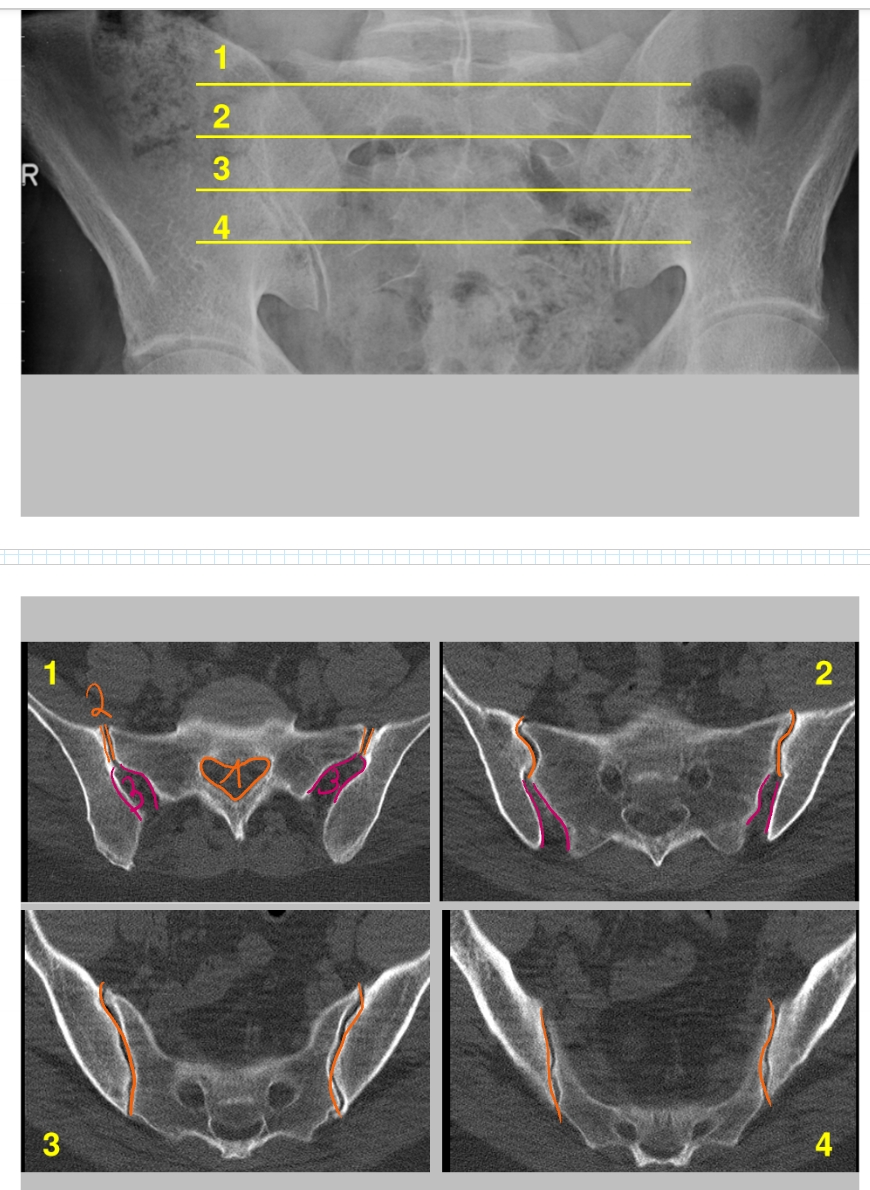

canalis sacralis

sacro-iliacaal gewricht

wordt groter naarmate verder naar beneden

sacro-iliacale ligamenten